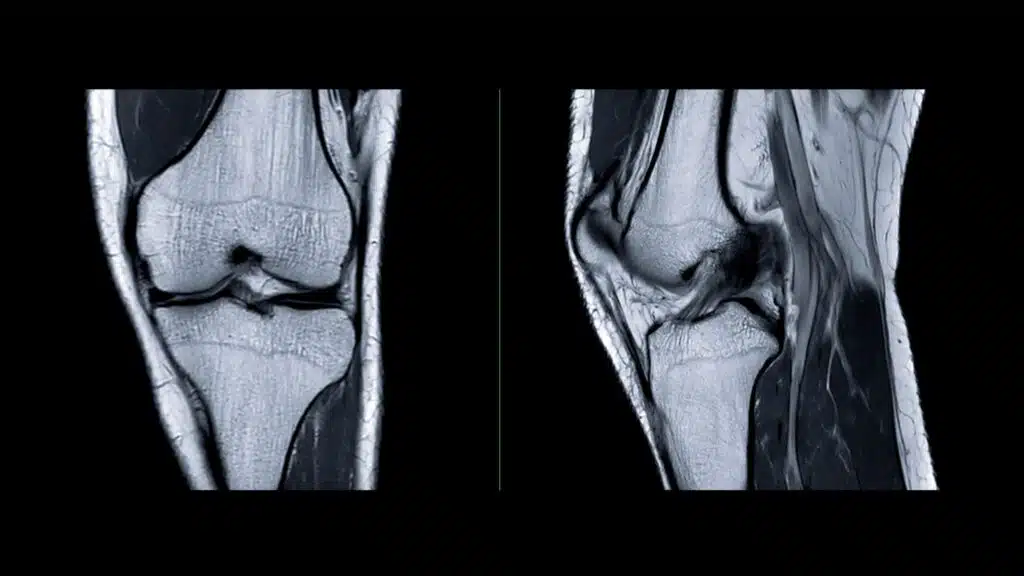

It’s a scenario familiar to many athletes and active individuals: a quick plant of the foot to change direction, followed by a sudden, unmistakable “pop” from deep within the knee. This moment often marks a significant disruption to a person’s athletic pursuits and daily life. The structure involved is frequently the anterior cruciate ligament, or ACL. This critical band of tissue runs through the center of the knee, providing essential stability and preventing the shin bone from sliding too far forward on the thigh bone, particularly during rotational movements like cutting, pivoting, and landing from a jump.